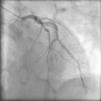

Case reportA 61-year-old man with no history of cardiac disease presented to a community hospital reporting typical chest pain 3hours in duration with more severe intensity in the last 30minutes. The initial standard 12-lead electrocardiogram (ECG) showed ST-segment elevation in leads V1–V5 and slight ST-segment elevation in the inferior leads (Fig. 1A). The patient was given 5000U of unfractionated heparin IV, 600mg clopidogrel oral loading dose and 300mg oral aspirin, and was transferred to our hospital for urgent catheterization. He arrived at our cath lab hemodynamically stable, with persistent chest pain. Coronary angiography, performed four and a half hours after symptom onset, showed a normal left coronary artery (Fig. 2) and patent main vessel of the codominant RCA. Left ventriculography was normal. Careful review of the coronary angiogram revealed proximal occlusion of the right ventricular (RV) branch of the RCA (Fig. 3A and B). The RV branch occlusion was managed with balloon dilation and stenting (2.0mm×12.0mm bare-metal stent at 16atm, Multi-Link Mini Vision®, Abbott Vascular, USA), resulting in resolution of the chest pain and ST-segment elevation (Figs. 1B and 3C). One hour after the procedure the patient experienced a new episode of chest discomfort and ST-segment changes similar to the initial ECG (re-elevation in leads V1–V4 and slight elevation in leads II, III, and aVF) (Fig. 1C). Emergency coronary angiography demonstrated acute stent thrombosis, which was probably related to previous inadequate stent covering of the proximal portion of the coronary plaque. Abciximab infusion was initiated, thrombus aspiration was performed and another proximal and overlapped bare-metal stent (2.25mm×12.0mm at 12atm, Multi-Link Mini Vision®, Abbott Vascular, USA) was implanted, again resulting in resolution of chest pain and ST-segment elevation. The peak troponin I level was 5.2ng/ml. The patient recovered without sequelae and was asymptomatic and fully active one month later. Contrast-enhanced magnetic resonance imaging (MRI) performed 30 days after presentation showed normal left ventricular function and normal right ventricular size and motion. No area of delayed hyperenhancement was visualized (Fig. 4).

Although it is usually considered that occlusion of a small nondominant right coronary artery is not associated with significant consequences, there are reports of cases presenting with sudden cardiac death.5 Importantly, there are also reports of sudden cardiac death in which autopsy confirmed the occlusion of a branch of the RCA causing isolated RVMI.6 Our case, to the best of our knowledge, is the first one reported of primary percutaneous coronary intervention treatment of an RV branch occlusion causing isolated acute RVMI and anterior ST-segment elevation. Acute stent thrombosis with recurrence of chest pain and anterior ST-segment re-elevation was successfully managed percutaneously. Revision of images of the first intervention showed that the proximal portion of the unstable coronary plaque was not covered by the stent. Another stent was implanted, proximal and overlapped to the previous one, to cover all the unstable plaque. Minimal myocardial necrosis was demonstrated by troponin assay and follow-up contrast-enhanced MRI showed no areas of delayed hyperenhancement in the right or left ventricles.